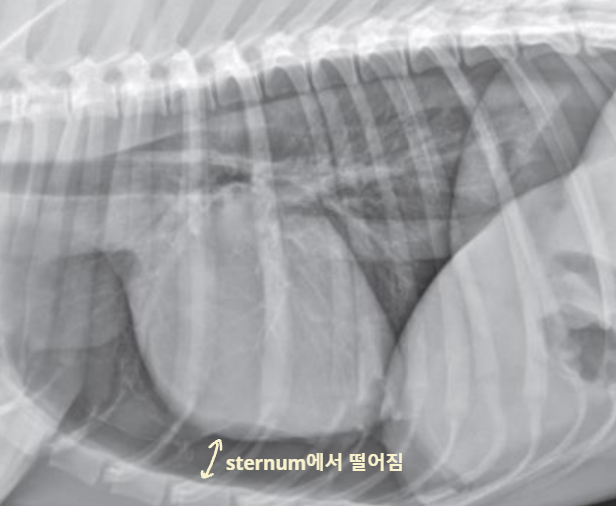

4. Pleural Space

| Pleural effusion (ํ์) | Pneumothorax (๊ธฐํ) | |

|---|---|---|

| ํ๊ฐ(pleural cavity)์ ๋ฌผ์ด ์ฐฌ ๊ฒ (ํ์ ์ฐจ๋ฉด โ ํ์์ข ) | ํ๊ฐ์ ๊ณต๊ธฐ๊ฐ ์ฐฌ ๊ฒ (ํ์ ์ฐจ๋ฉด โ ํ๊ธฐ์ข ) | |

| Radiographic signs interlobar fissure ๋๊ป๊ฒ ๊ด์ฐฐ๋๊ณ , ํ๋ฒฝ์ด ๋จ์ด์ ธ ๋๊ฐ ๊ฒ์ฒ๋ผ ๋ณด์ | Radiographic signs ์ฌ์ฅ์ด ๋ ์๊ณ , ํ๊ฐ ์ชผ๊ทธ๋ผ๋ฆ | |

| - Interlobar fissure widening - Lung retraction - Pleural wall thickening - Scallop sign - Cardiac effacement - Blunt angle | - Retraction of pleural surface - Collapsed lung (โ opacity ์ฆ๊ฐ) | |

![]() | ![]() | |

![]() ![]() | ![]() ![]() | |